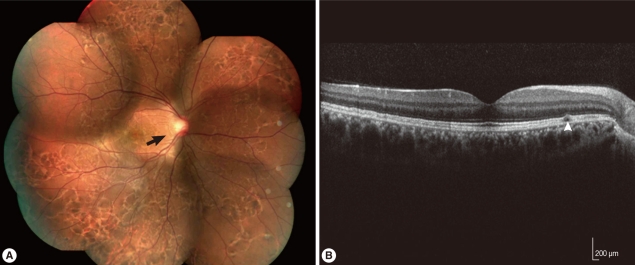

Imported Intraocular Gnathostomiasis with Subretinal Tracks Confirmed by Western Blot Assay

The Korean Journal of Parasitology 2012;50(1):73-78.